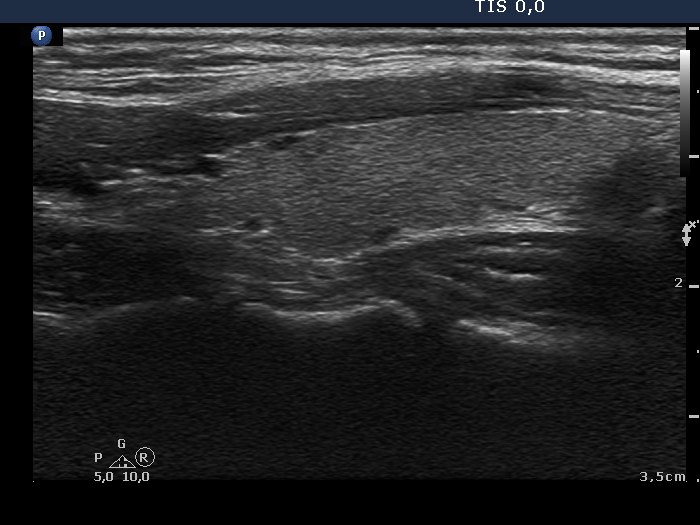

The borders of the nodule - case conp 010 (ultrasonographic picture 7)

Left lobe, longitudinal scan.